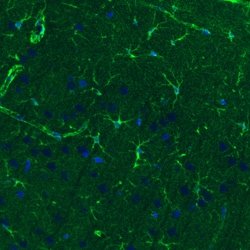

Invitrogen™ Glutamine Synthetase Monoclonal Antibody (CL3004)

Glutamine synthase is part of the glutamine synthetase family. Ammonia incorporation in animals occurs through the actions of glutamate dehydrogenase and glutamine synthase. Glutamate plays the central role in mammalian nitrogen flow, serving as both a nitrogen donor and nitrogen acceptor. It also has an important role in controlling metabolic regulations of neurotransmitter glutamate. Because of the multiple functions and importance of GS in cellular metabolism, both catalytic activities and synthesis are highly regulated. The activity of GS is controlled by adenylylation. Its activity is decreased in the cerebral cortex of brains affected by Alzheimer's disease, particularly in the vicinity of senile plaques. It is also decreased under conditions of glucose deprivation.